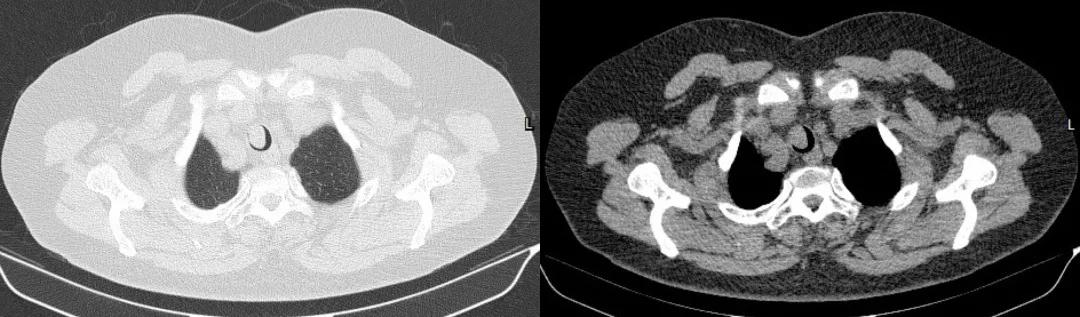

胸部CT:

胸部CT(冠状位)

四、影像学检查:表现为气管腔内的软组织密度肿块

表现为气管腔内的软组织密度肿块,多为偏心性,好发于气管后壁、气管软骨,低中度均匀强化,伴气管壁增厚,管腔不规则狭窄。有时可见气管旁淋巴结肿大,提示肿瘤转移可能。晚期可血行转移至肺、骨、脑、肝脏。